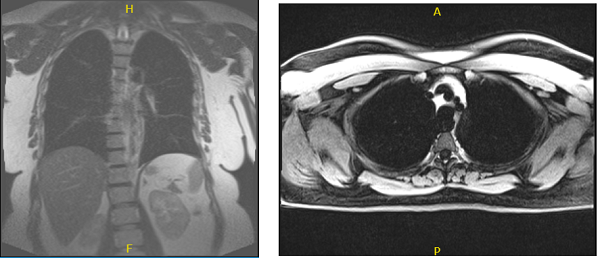

We discussed at length to continue seeing a Neurologist for tremors and speech issues, Psychologist and psychiatrist for depression and anxiety, Pain physician for back and neck pain, primary care doctor for pedal edema. Will get an MRI for the chest for the nape of neck swelling in the supraclavicular region of both sides.

MRI were viewed and discussed; Thyroid: Unremarkable, without lesion, mildly limited assessment due to signal dropout over the neck region. Lungs: No focal lesion or diffuse lung pathology.

No pleural effusion. Mediastinum: No mediastinal or hilar adenopathy. Unremarkable cardiovascular structures. No pericardial effusion. No aortic aneurysm or coarctation. Patent arch great arteries.

Thoracic spine and chest wall: Mild dextrocurvature of the thoracic spine, otherwise unremarkable. Upper abdomen: No abnormality in the visualized portion of the upper abdominal organs.

MRI chest without and with contrast